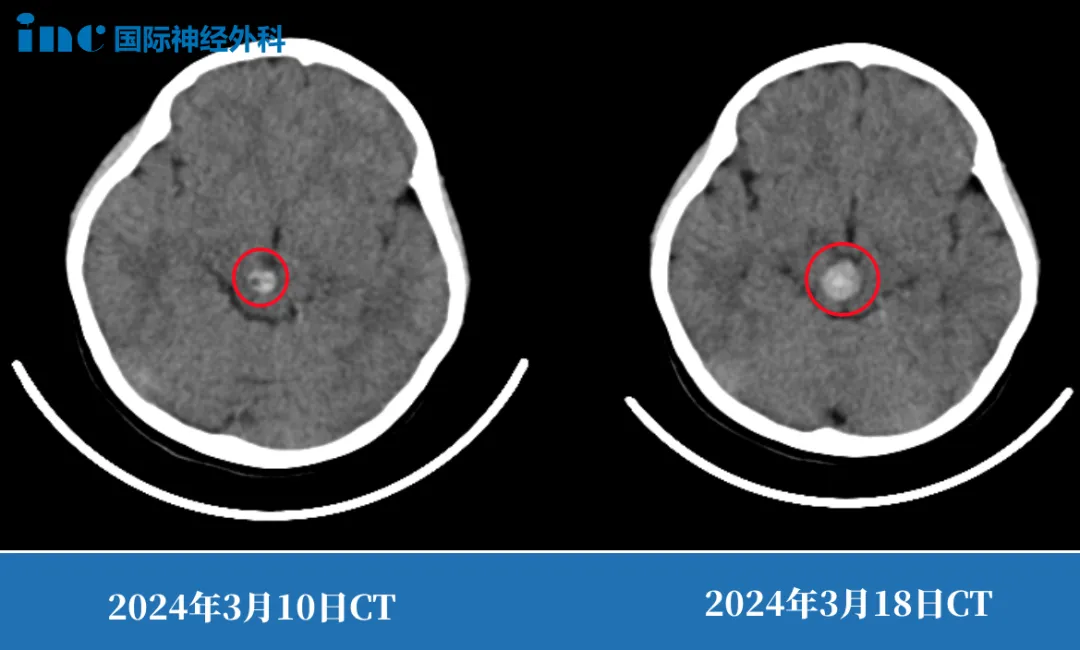

就在多多父母踌躇该怎么办的时候,第二次出血来袭,由于肿瘤对动眼神经核的破坏,此时的多多已经出现严重的动眼神经麻痹,一只眼睛眼皮无法抬起、瞳孔散大。

也就是说,那颗藏在脑干深处的血管瘤,第一次出血时只是“小漏”,破坏了部分动眼神经核(控制眼球运动和睁眼的神经);

而第二次出血直接“决堤”,不仅压迫了更多神经,还让本就脆弱的脑干功能岌岌可危。